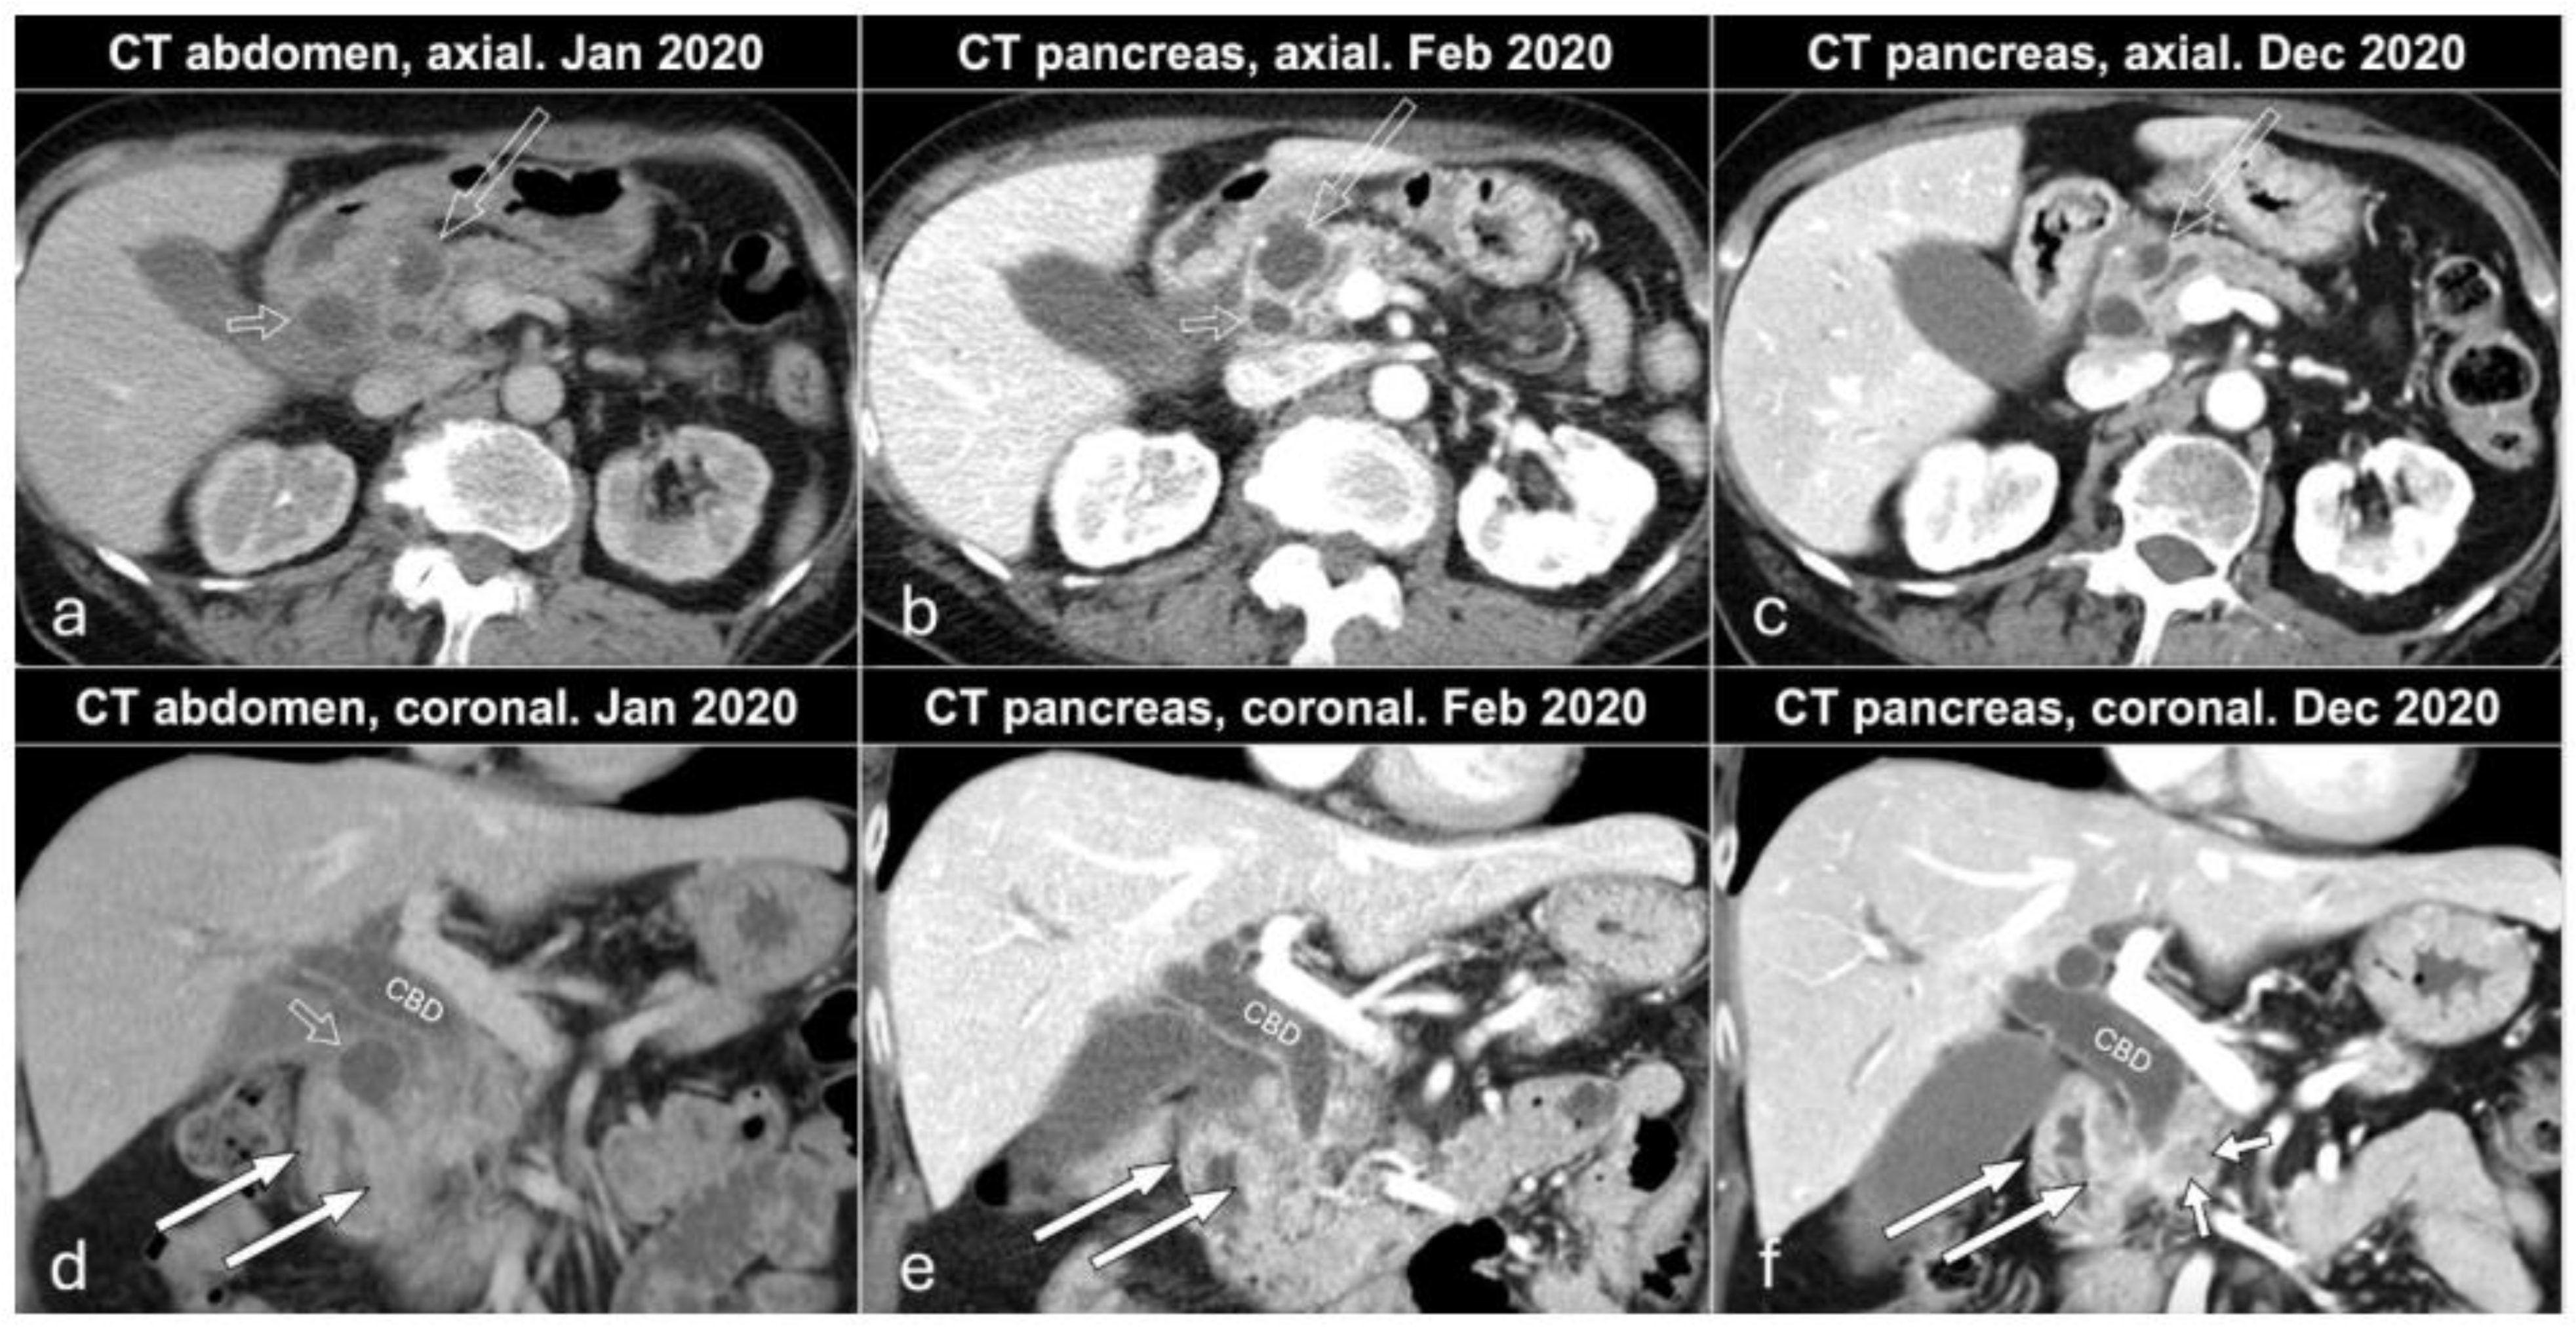

A 68-year-old female presented at a primary care outpatient clinic in January 2020 due to abdominal pain, weight loss (11 kg in total in one year), and frequent (7–9 per day) watery stools (sometimes fatty/oily stools). The patient had a 45-year history of smoking (approximately 15 pack-years of smoking) and very rarely drank alcohol. She had a 20-year history of kidney stones, and her abdominal pain disappeared after treatment with non-steroid anti-inflammatory drugs (NSAIDs) and tramadol. The patient was clinically diagnosed as suffering pain related to kidney stones, which was confirmed with computed tomography (CT) of the kidneys showing five stones < 5 mm in the right kidney and three stones < 5 mm in the left kidney. Routine laboratory results showed slightly elevated liver function tests (aspartate aminotransferase 0.7 μkat/L, alanine transaminase 1.05 μkat/L, and alkaline phosphatase 2.2 μkat/L), and CT of the abdomen and pelvis was performed (Figure 1a,d). In summary, there were inflammatory changes in the head of the pancreas, hepatoduodenal ligament, and peripancreatic fat, wall thickening of the second part of the duodenum, presence of cystic lesions in the pancreatic groove, and head and regional lymphadenopathy. Additionally, there was dilatation of the common bile duct (1.6 cm) and mild dilatation of the main pancreatic duct in the body and tail of the pancreas (5 mm) (Figure 1a,d). Gastroscopy in January 2020 showed mild bleeding of the edematous and vulnerable mucosa in duodenal pars descendens. The endoscopist described in the report that in this part of the duodenum the passage was somehow difficult and the expansion of the duodenal lumen after CO2 insufflation was not fully successful. There were no signs of ulcerations or tumor. Biopsy was performed, and the histopathology showed normal mucosa and Brunner glands. The patient was referred to a surgeon (February 2020), who started treatment with esomeprazole (due to the endoscopic findings) and pancreatic enzyme replacement therapy (PERT) (due to the history of weight loss and steatorrhea). The case was presented and discussed at the multidisciplinary team (MDT) pancreas conference at our hospital, and the team recommended CT of the pancreas and endoscopic ultrasound (EUS). CT of the pancreas (February 2020) confirmed the findings of inflammatory changes in the head of the pancreas, hepatoduodenal ligament, and peripancreatic fat, wall thickening of the second part of the duodenum (more prominent changes in the medial aspect of duodenum compared to the examination in January 2020), regional lymphadenopathy and dilatation of the common bile, and mild dilatation of the main pancreatic duct in the body and tail of the pancreas (Figure 1b,e). One of the cystic lesions in the head of the pancreas increased from 2 to 2.5 cm, whereas another cystic lesion in the pancreatic groove decreased from 2 to 1 cm.

In December 2020, the patient came for a clinical check-up at the pancreatic outpatient clinic. Clinical examination showed jaundice, and laboratory tests showed elevated liver function tests (aspartate aminotransferase 4.06 μkat/L, alanine transaminase 9.01 μkat/L, gamma-glutamyl transferase 40.4 kE/L, alkaline phosphatase 11.5 kE/L, bilirubin 89 μmol/L), CA 19-9 (199 kE/L), IgG4 (2.82 g/L), and CRP (9 mg/L). CT of the pancreas showed mild regress of the inflammatory changes in the area and of the cystic lesions in the pancreatic groove and head, as well as of the regional lymphadenopathy. Wall thickening of the medial aspect of the second part of the duodenum remained, and additionally, there was a newly appearing hypovascular 1.5 cm solid mass medially in the head of the pancreas, which caused a further dilatation of the common bile duct from 1.6 to 2 cm (whereas the main pancreatic duct in the body and tail of the pancreas remained unchanged at 5 mm) (Figure 1c,f). After discussion at an MDT conference, a Whipple’s procedure was performed. Gross examination of the specimen after axial slicing showed a poorly circumscribed 1.6 cm solid yellow-white tumor in the pancreatic head with suspected invasion of the peripancreatic fat, ampulla of Vater, common bile duct, duodenal wall, and resected part of the superior mesenteric vein (Figure 2). Cranial to the tumor, in the region of the anterior pancreatoduodenal groove, a 2.4 cm non-mucinous unilocular cyst with a fibrotic wall was found (Figure 3). No papillary structures or obvious communication with the duct system were seen. The surrounding pancreatic and peripancreatic tissue showed fibrosis, and in the adjacent duodenum, a diffuse thickening of the mucosa and submucosa was noted.

Figure 1. Axial (ac) and coronal (df) contrast-enhanced images of CT abdomen in January (a,d) and CT pancreas in February (b,e) and December (c,f) 2020. CBD: common bile duct; open white arrows: cystic lesion in the pancreatic head; open short white arrows: cystic lesion in the pancreatic groove; white arrows: wall thickening of the descending portion of duodenum; short white arrows: pancreatic cancer.